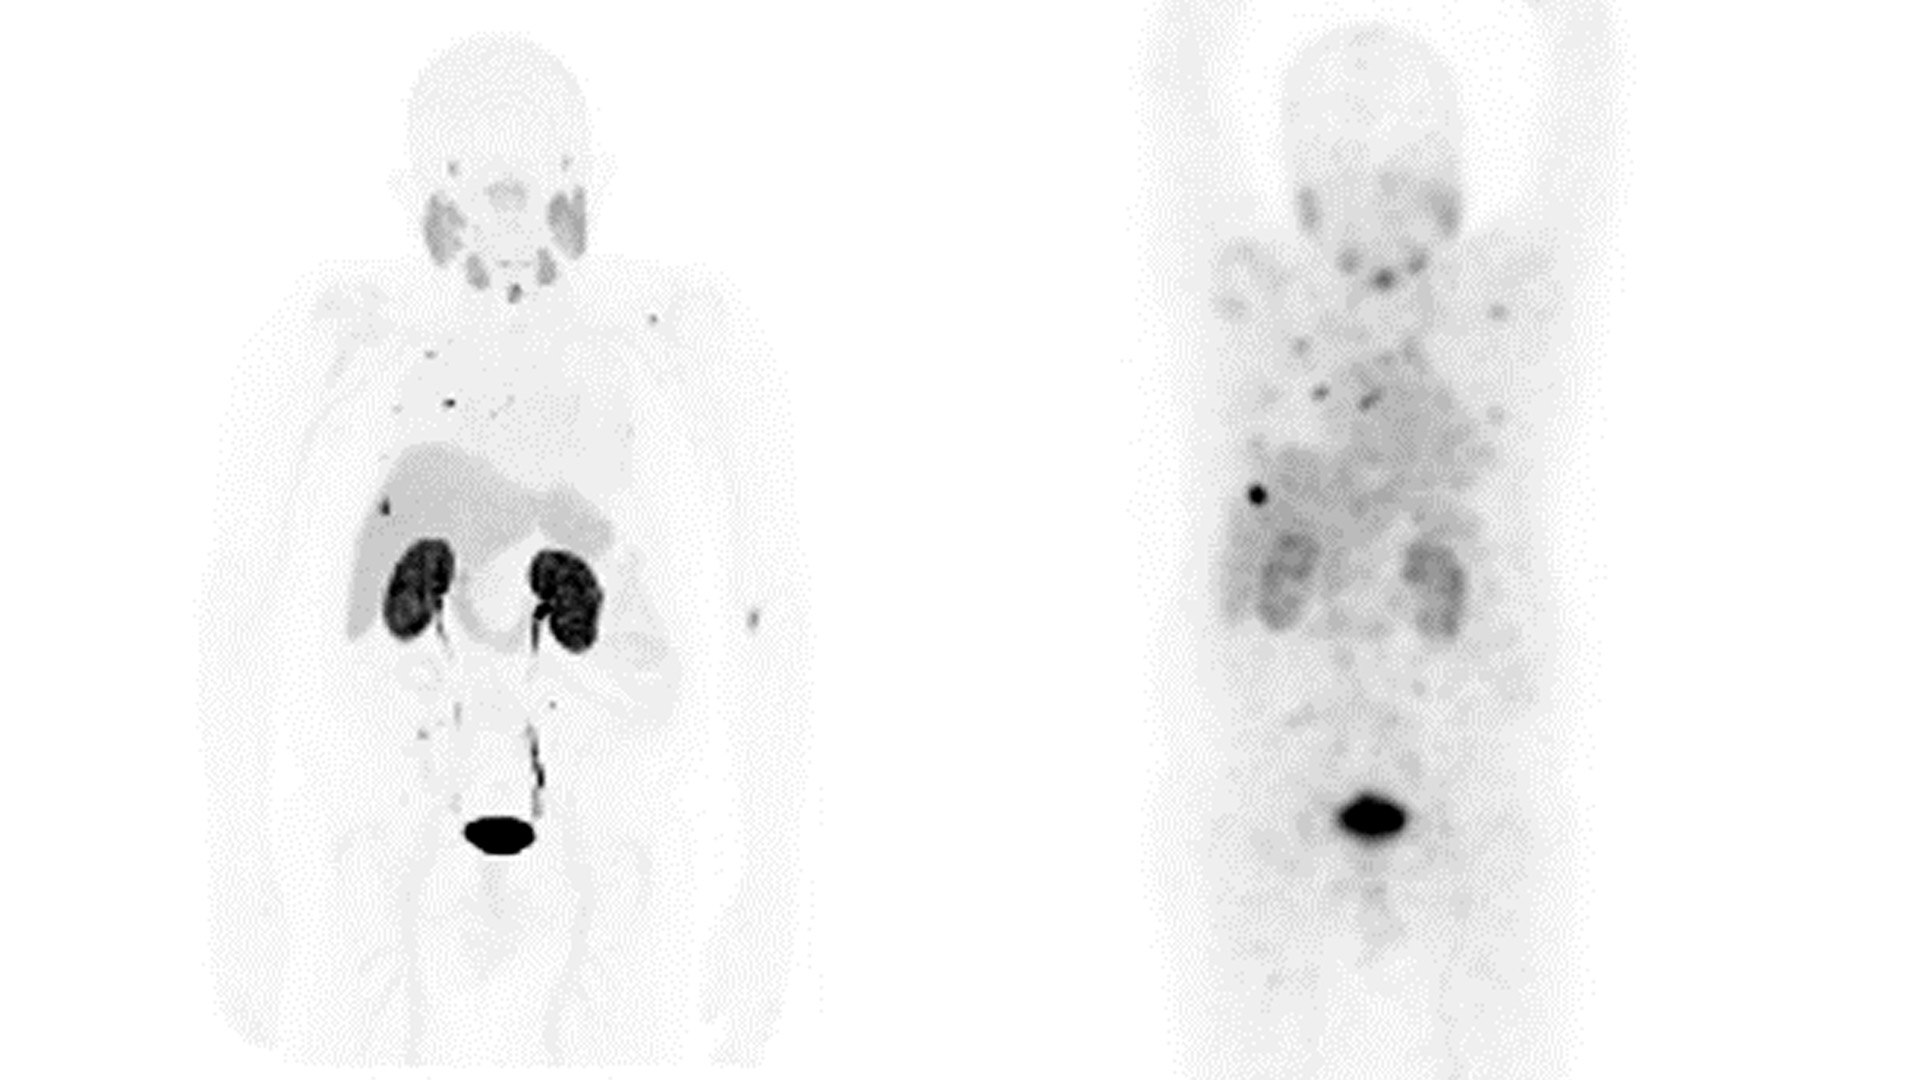

Диагностика

Компания GE HealthCare предоставляет новаторские решения, которые обеспечивают непревзойденный уровень чувствительности и повышают точность диагностики

Наш специальный ассортимент диагностических решений для визуализации, ориентированных на тераностику, был разработан специально для удовлетворения потребностей врачей и пациентов сегодня и в будущем.

Визуализация и мониторинг в сочетании с терапией

Компания GE HealthCare уже сегодня формирует будущее в области диагностики с помощью решений для более точной визуализации и мониторинга, а также инновационных решений в области лечения.